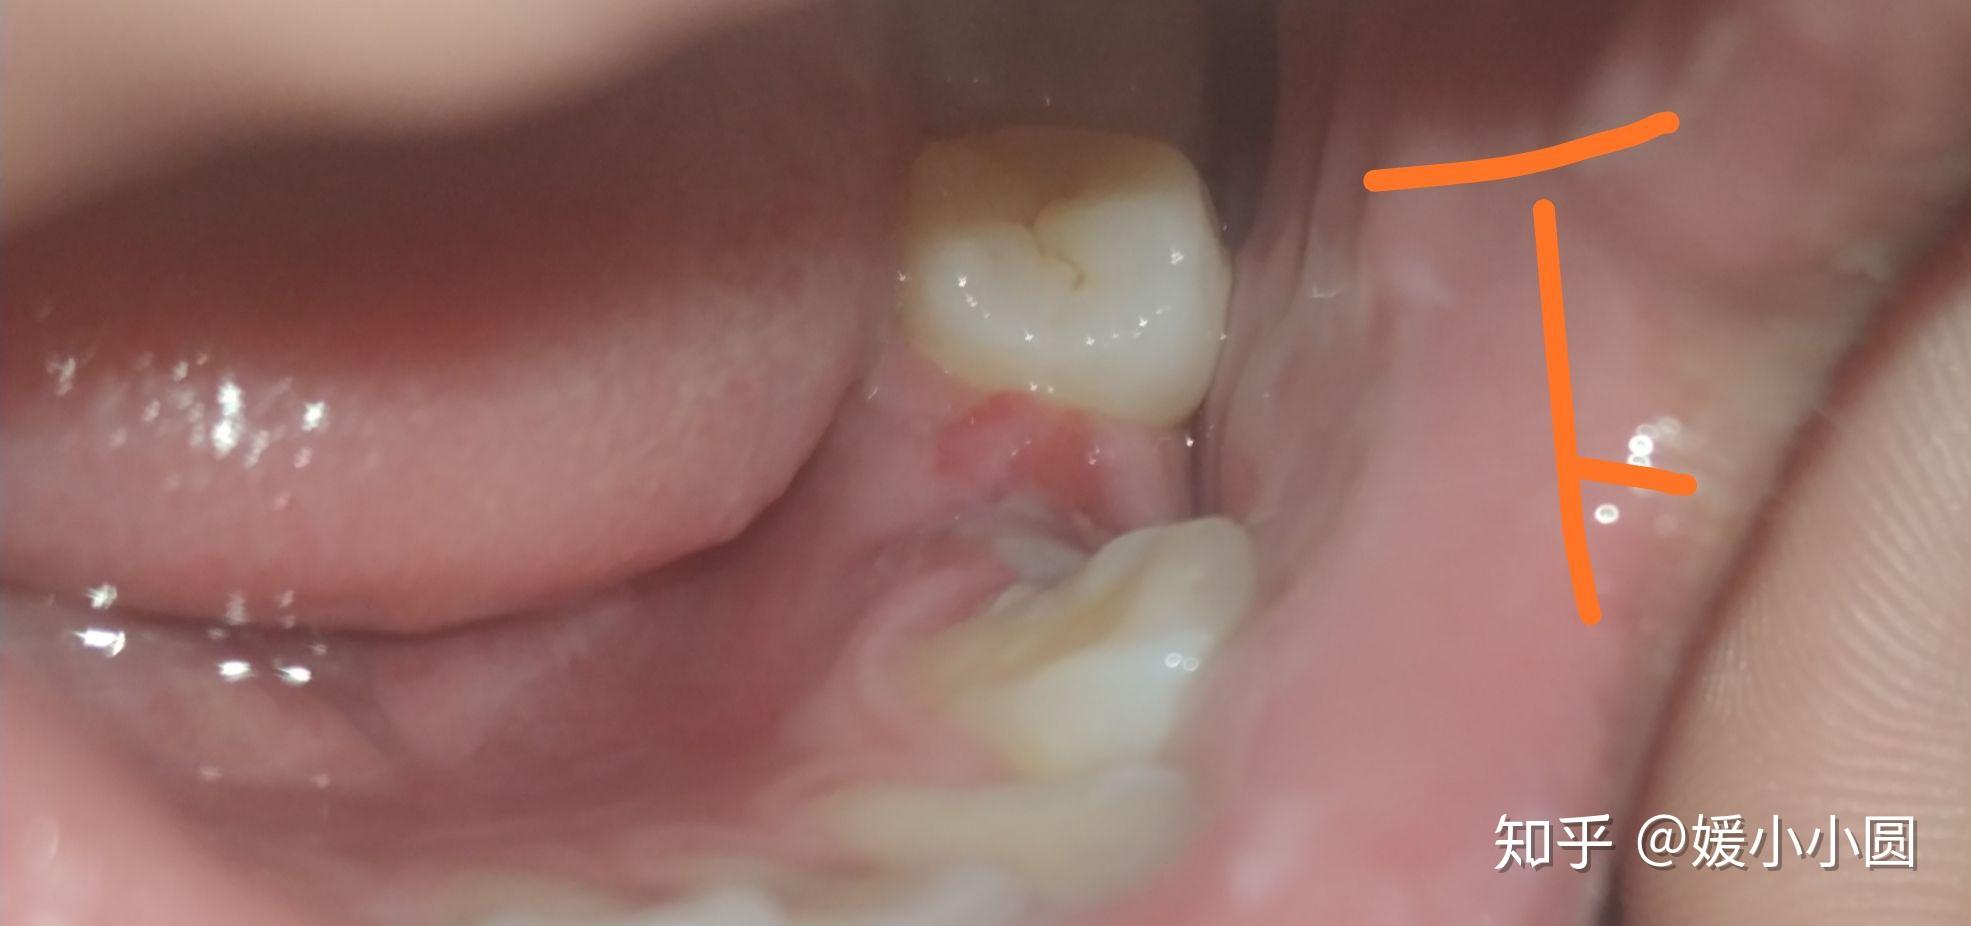

拔智齿的第八天拆线了但是有个黑洞要怎么办啊